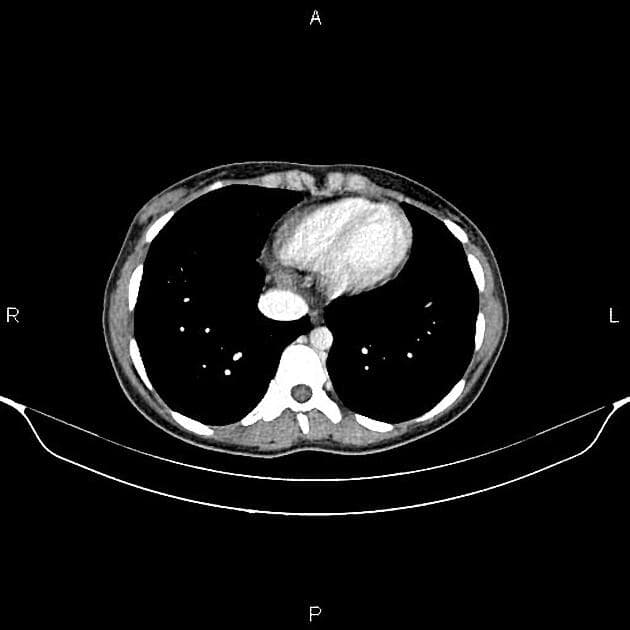

Axial Gradient Echo

Có các dấu hiệu viêm hoạt động ảnh hưởng đến đoạn cuối ruột non và đoạn đầu ruột già: dày thành ruột (mural thickening), phù (edema), hạn chế khuếch tán (restricted diffusion) và tăng quang sau tiêm thuốc đối quang ở đoạn cuối 30 cm của ruột non và manh tràng (cecum). Mô hình tăng quang có dạng mục tiêu (targetoid), với tăng quang ở lớp niêm mạc và thanh mạc. Trong đoạn ruột bất thường này, có các đoạn ngắn không bị tổn thương, tại đó thấy các túi nhỏ ở bờ đối mạc tràng (anti-mesenteric border sacculation). Phía trên đoạn bệnh lý, có hiện tượng giãn nhẹ. Ngoài ra, ghi nhận sự tăng sinh mỡ ở vùng hạ vị phải, làm tách biệt các quai ruột bị bệnh khỏi các quai ruột còn lại trong ổ bụng. Có thể thấy hình ảnh hình thành đường rò giữa hồi tràng và manh tràng liền kề. Có nhiều hạch bạch huyết viêm trong mạc treo ruột non. Không thấy hình ảnh (no evidence of) tổn thương ở ruột non đoạn gần hoặc các đoạn khác của đại tràng. Các đoạn ruột viêm có nhu động giảm. Không thấy hình ảnh dịch tự do hoặc ổ dịch trong ổ bụng hay tiểu khung.

Hình ảnh cho thấy các đặc điểm điển hình của bệnh viêm hoạt động, bao gồm dày thành ruột và phù, tăng quang dạng lớp (layering enhancement), hạn chế khuếch tán, mỡ bao quanh (fat wrapping), và tạo túi giả dọc theo bờ đối mạc tràng. Ngoài ra, có bằng chứng của bệnh lý xuyên thành (transmural disease) với hình thành đường rò giữa hồi tràng và manh tràng.